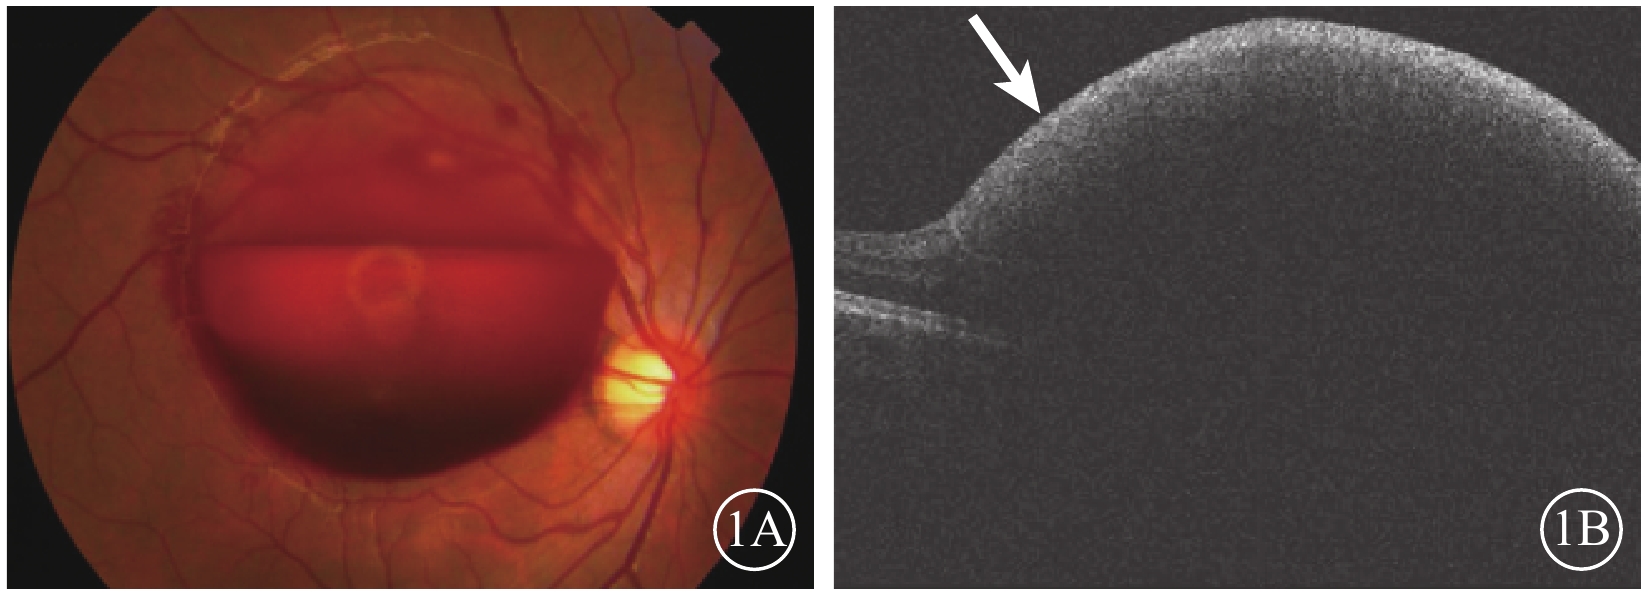

患者男,20歲。因右眼視力突然下降伴眼前黑影遮擋于2015年11月30日來我院就診。患者訴1周前右眼視力突然下降伴眼前黑影遮擋,視物呈紅色;無眼紅、眼痛、畏光、流淚。既往雙眼視力正常;視力下降前有咳嗽史,視力下降當天曾用力排便。否認飲酒、外傷史以及高血壓病、糖尿病、血液病等全身系統性疾病。血壓:113/63 mmHg(1 mmHg=0.133 kPa);眼科檢查:右眼視力數指/15 cm,不能矯正;左眼視力0.3,矯正視力1.2。右眼眼壓12 mmHg,左眼眼壓14 mmHg。左眼眼前節及眼底檢查未見異常。右眼眼前節檢查未見異常。眼底視盤邊界清楚,色澤淡紅;黃斑區類圓形隆起視網膜前出血,直徑約6個視盤直徑(DD),其余視網膜平復,未見出血及滲出(圖1A)。熒光素眼底血管造影(FFA)檢查,黃斑區前半月形出血遮蔽熒光灶,其余視網膜未見明顯異常熒光。光相干斷層掃描(OCT)檢查,黃斑視網膜前強反射,遮擋其后組織結構回聲(圖1B)。實驗室血尿常規、生物化學及凝血機制等檢查結果無異常。診斷:右眼Valsalva視網膜病變。

圖1

右眼彩色眼底、OCT像。1A. 彩色眼底像,黃斑區視網膜前6 DD大小出血區,遮蔽黃斑;1B. OCT像,視網膜前強反射信號(白箭),其下方視網膜組織反射信號消失

圖1

右眼彩色眼底、OCT像。1A. 彩色眼底像,黃斑區視網膜前6 DD大小出血區,遮蔽黃斑;1B. OCT像,視網膜前強反射信號(白箭),其下方視網膜組織反射信號消失

患者男,20歲。因右眼視力突然下降伴眼前黑影遮擋于2015年11月30日來我院就診。患者訴1周前右眼視力突然下降伴眼前黑影遮擋,視物呈紅色;無眼紅、眼痛、畏光、流淚。既往雙眼視力正常;視力下降前有咳嗽史,視力下降當天曾用力排便。否認飲酒、外傷史以及高血壓病、糖尿病、血液病等全身系統性疾病。血壓:113/63 mmHg(1 mmHg=0.133 kPa);眼科檢查:右眼視力數指/15 cm,不能矯正;左眼視力0.3,矯正視力1.2。右眼眼壓12 mmHg,左眼眼壓14 mmHg。左眼眼前節及眼底檢查未見異常。右眼眼前節檢查未見異常。眼底視盤邊界清楚,色澤淡紅;黃斑區類圓形隆起視網膜前出血,直徑約6個視盤直徑(DD),其余視網膜平復,未見出血及滲出(圖1A)。熒光素眼底血管造影(FFA)檢查,黃斑區前半月形出血遮蔽熒光灶,其余視網膜未見明顯異常熒光。光相干斷層掃描(OCT)檢查,黃斑視網膜前強反射,遮擋其后組織結構回聲(圖1B)。實驗室血尿常規、生物化學及凝血機制等檢查結果無異常。診斷:右眼Valsalva視網膜病變。

圖1

右眼彩色眼底、OCT像。1A. 彩色眼底像,黃斑區視網膜前6 DD大小出血區,遮蔽黃斑;1B. OCT像,視網膜前強反射信號(白箭),其下方視網膜組織反射信號消失

圖1

右眼彩色眼底、OCT像。1A. 彩色眼底像,黃斑區視網膜前6 DD大小出血區,遮蔽黃斑;1B. OCT像,視網膜前強反射信號(白箭),其下方視網膜組織反射信號消失